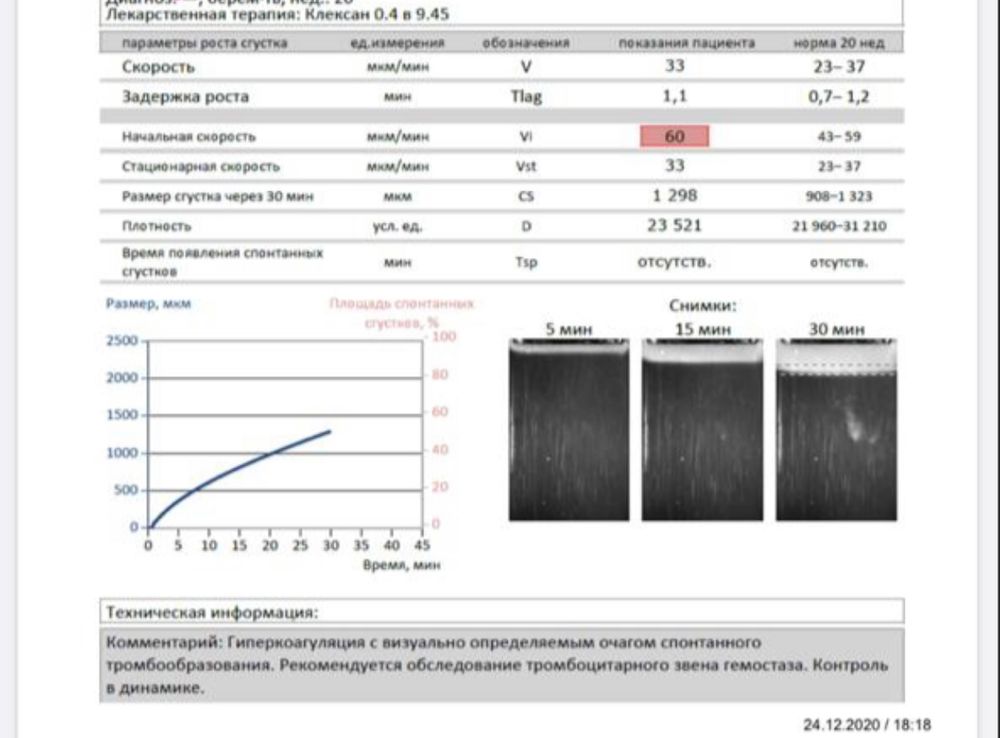

сейчас картина изменилась и неприятная ,тромбодинамика тоже показывает изменения «гиперкоагуляция,с визуально определяемым очагом спонтанного тромбообразования» (прикрепляю фото тр-динам)